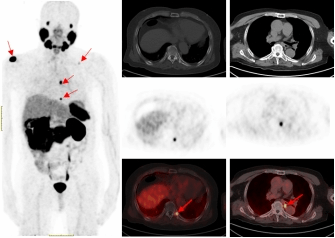

PSMA-PET/CT利用靶向核素分子影像优势,可识别最大直径为4毫米甚至更小的转移淋巴结,68Ga标记的PSMA-PET/CT诊断骨转移灶敏感性更高,能比传统检查手段早一步发现转移灶,为患者的精准治疗赢得时间。

一名75的岁男性患者自2019年确诊前列腺癌后,先后接受过两次内分泌治疗及前列腺癌根治术的综合治疗。在术后两年的复查中发现血PSA持续升高,CT检查和全身骨显像检查均未发现明显异常,医生建议随诊,患者来到伟德victor1946附属医院要求进一步检查。经核医学科68Ga-PSMA PET/CT检查后结果显示,双侧肩胛骨、左侧第9后肋、第2腰椎及纵隔淋巴结均已存在癌症转移。